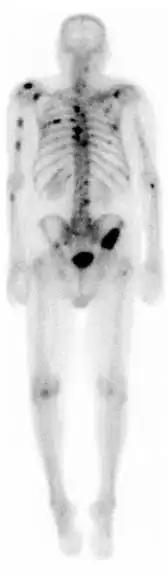

![]() A nuclear medicine whole-body bone scan. The nuclear medicine whole-body bone scan is generally used in evaluations of various bone-related pathology, such as for bone pain, stress fracture, nonmalignant bone lesions, bone infections, or the spread of cancer to the bone. | |